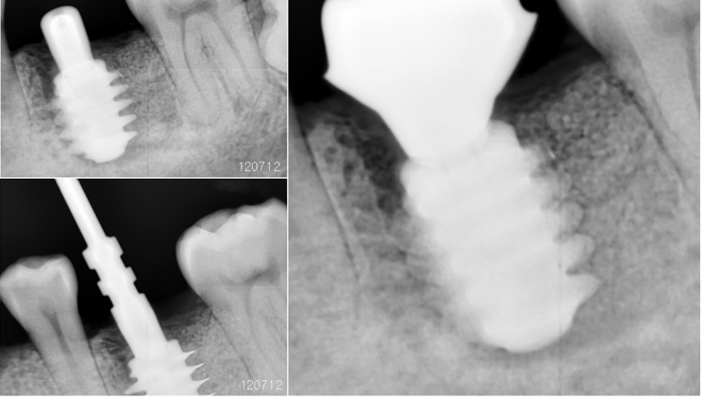

Clinical case: Bone filling into the bottom of deepest thread at 8.0mm AnyRidge fixture

- Courtesy of Dr. Kwang Bum Park -

Keywords

AnyRidge, Knifethread ,extraction socket, ,initial stability ,Allograft, ,osseointegratio ,Dr. Kwang Bum Park, , Mandibular, Single replacement, AnyRidge, Mega-oss,

Products used

Implant system-AnyRidge, Regeneration-Mega-Oss

How can primary stability be increased?

Primary stability is especially important in the case of poor quality bone. The instability of dental implants results in fibrous encapsulation and failed osseointegration (Lioubavina-Hack, et al. 2006). One method for increasing primary stability is modifying the surgical technique for implant placement. Studies have reported that the undersized surgical technique, which uses a final drill diameter smaller than the diameter of the implant, results in a higher primary stability when compared with the press-fit technique (Tabassum, et al. 2009, Tabassum, et al. 2010a).

Ti implants with a deeper thread depth provide a higher surface area, which is advantageous for increasing stability in areas of poor quality bone (Abuhussein, et al. 2010). Ti implants with deeper thread depths also facilitate an increased load and mechanical interlocking with poor quality bone.